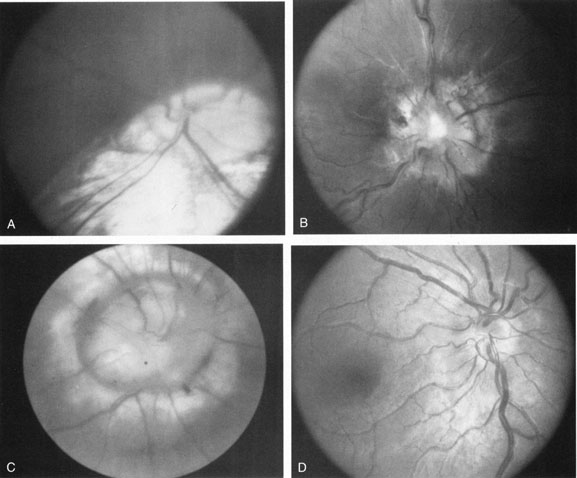

Optic disc colobomata (Fig. 6), if bilateral, may be seen in association with congenital nystagmus. Of greater import, however, is the association of colobomas or other dysplastic optic discs with basal encephaloceles, particularly in conjunction with hypertelorism, midfacial anomalies, or tongue-shaped retinochoroidal pigmentary disturbances.34 The morning glory disc syndrome, although typically unilateral, does not present in association with nystagmus, but rarely may be seen with midline central nervous system defects and endocrinopathies as well.35

Fig. 6. Spectrum of congenital disc anomalies. A. Large coloboma involving optic nerve and inferior retina. B. Dysplastic disc, central cup filled with fibroglial tissue. C. Morning glory disc anomaly. D. Markedly hypoplastic optic nerve. E. Coloboma of optic nerve without retinal involvement.